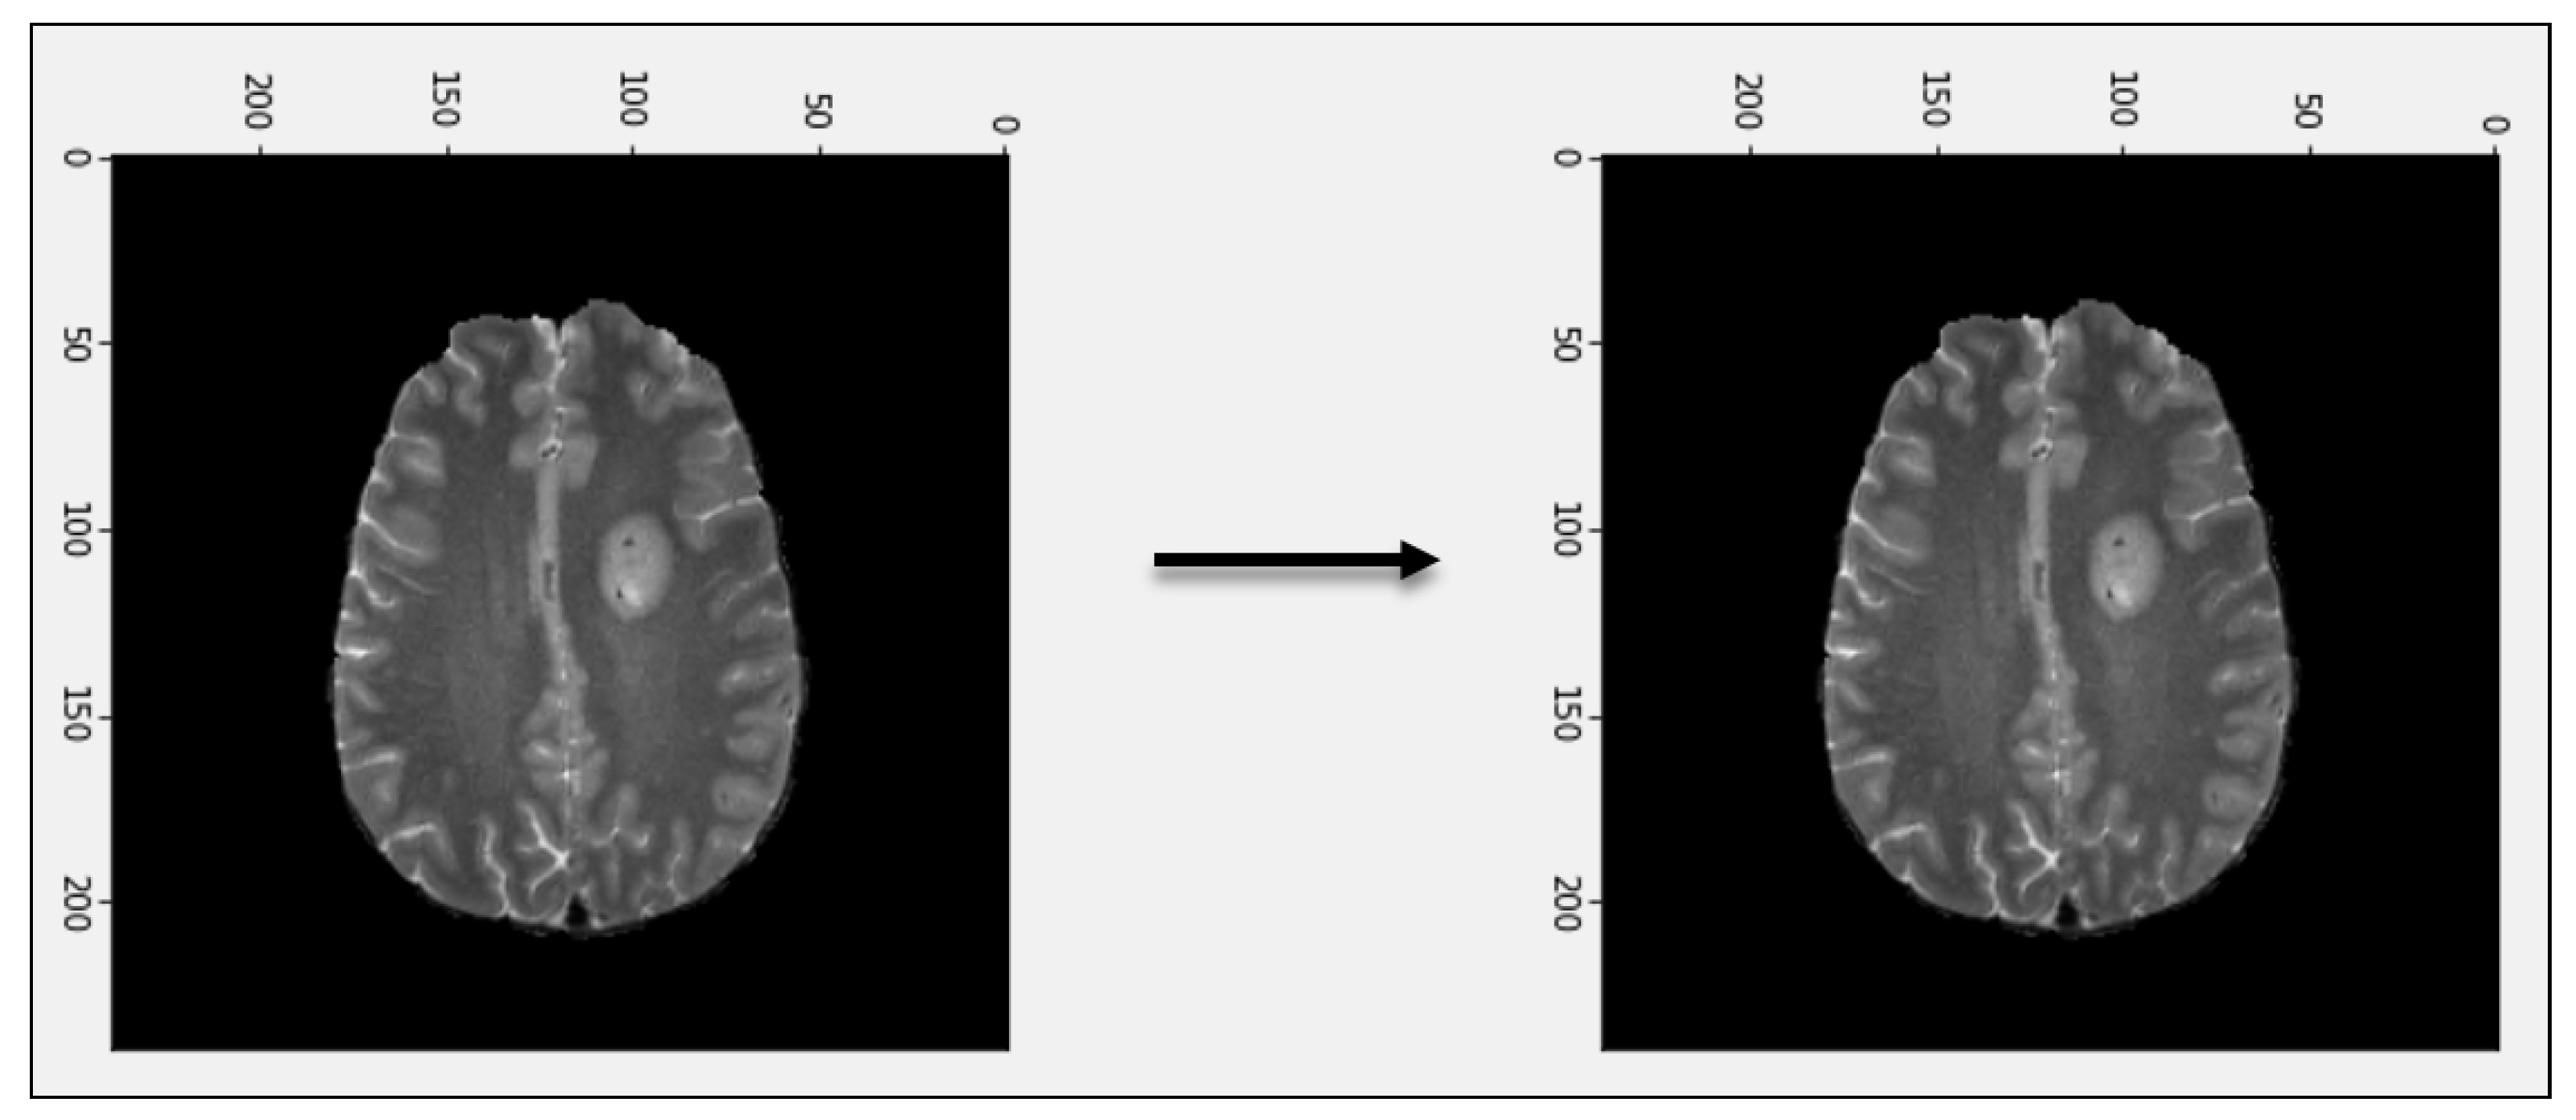

3.1. Pre-Processing